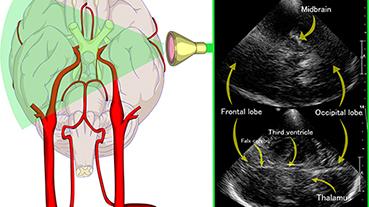

Innovative technologies and alternatives to traditional treatments are transforming the diagnosis and management of neurological conditions. In 2025, NewYork-Presbyterian physicians and surgeons from Columbia and Weill Cornell Medicine used sonication and convection-enhanced delivery to penetrate the blood-brain barrier, validated an adjunctive treatment for subdural hematoma, broadened access to spine surgery, advanced experimental therapies for neurodegenerative diseases, and more. Our specialists have been steadfast in reshaping the fields of neurology and neurosurgery in the pursuit of better patient outcomes and enhanced quality of care.

From cutting-edge research to compassionate patient practice, neurologists and neurosurgeons from Columbia and Weill Cornell Medicine are at the forefront of developing and applying the most advanced approaches to treat debilitating conditions affecting the brain and spine. With a broad range of focus on neurodegenerative and neurovascular disorders to malignant tumors, our innovative and advanced care is leading to new treatment options and enabling patients to achieve the best possible outcomes.